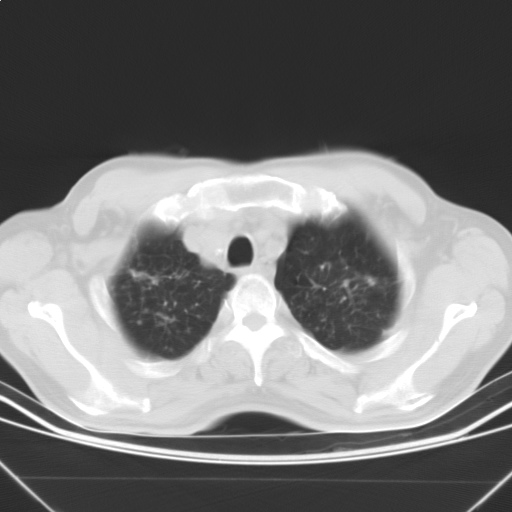

以下是引用随光逐影在2009-5-1 13:53:00的发言:[br]考虑为:1)两肺血行播散型肺结核;2)右肺下叶炎症感染。3)右侧胸膜增厚。